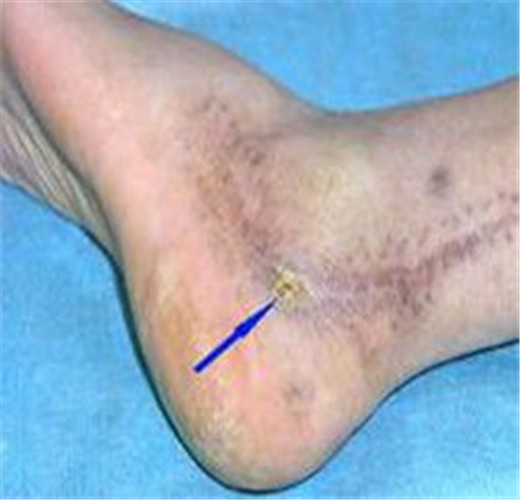

骨髓炎圖片

慢性骨髓炎症狀表現